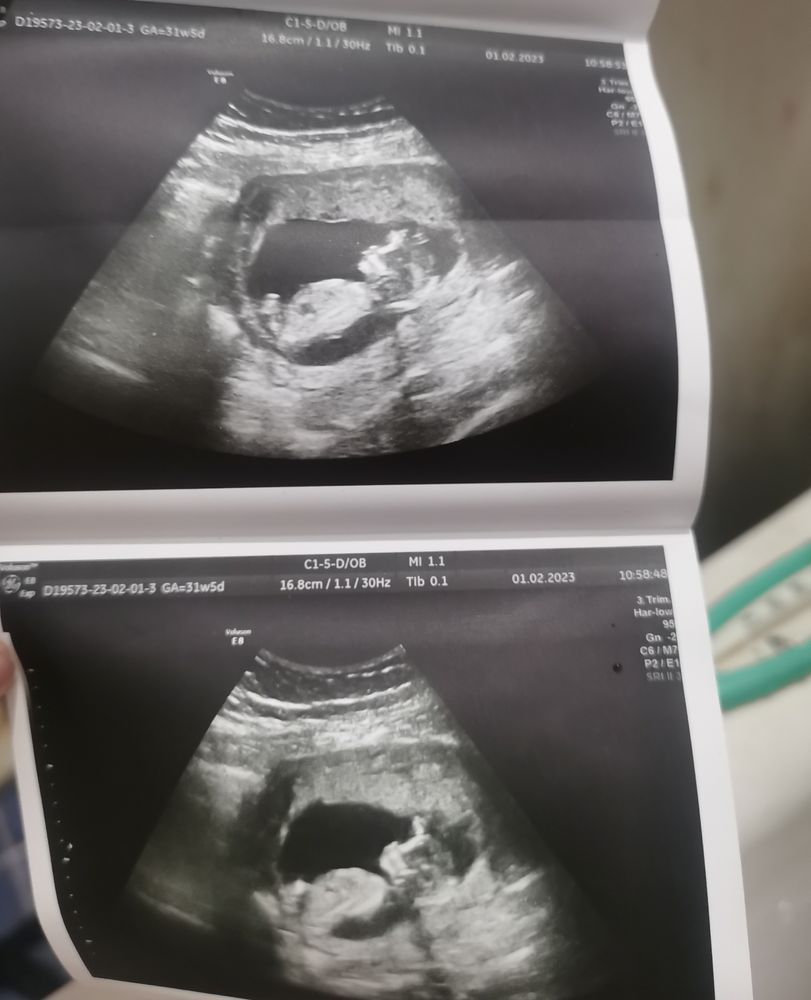

Моя креветочка♥️♥️♥️♥️

FOmKa , на боковом уж как-то вверх торчит. Сравните фото дочки если есть на таком сроке,череп именно,у кого милее

Natalija , увы, на таком нету. Есть уже пуська недели на 34 .... Там по одному только личику и правда можно было бы сказать что девочка. Нежные гладкие черты лица. А тут резкие. Ну может потому что маленький еще а может вы и правы , парень. Но поведение конечно совсем не дочкино

Господи, какой уже красивый человечек.. рада за вас!) сейчас всплакнула даже.. ведь срок у меня такой же был бы..